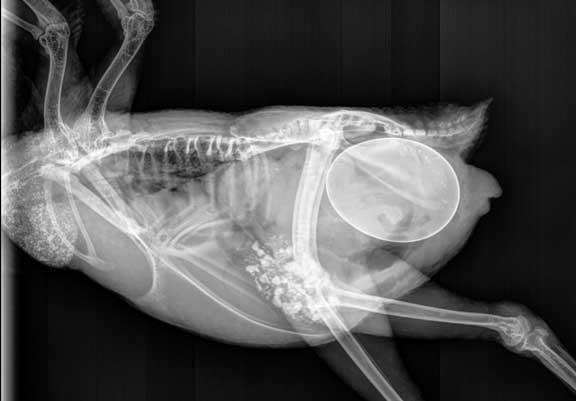

Para confirmar o diagnóstico, a radiografia é o exame mais utilizado, permitindo visualizar a posição, o tamanho e a calcificação do ovo. Em alguns casos, a ultrassonografia auxilia na avaliação do conteúdo abdominal e na detecção de peritonite por gema.